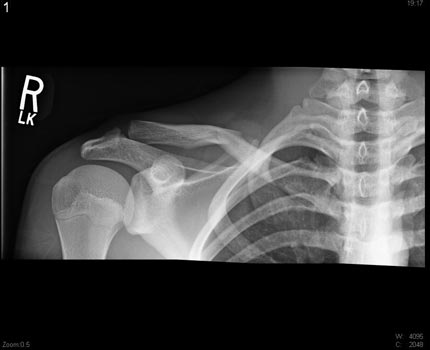

X-ray of the right shoulder area demonstrating a fracture of the clavicular bone.

Note: Images are shown for illustrative purposes. Do not attempt to draw conclusions or make diagnoses by comparing these images to other medical images, particularly your own. Only qualified physicians should interpret images; the radiologist is the physician expert trained in medical imaging.